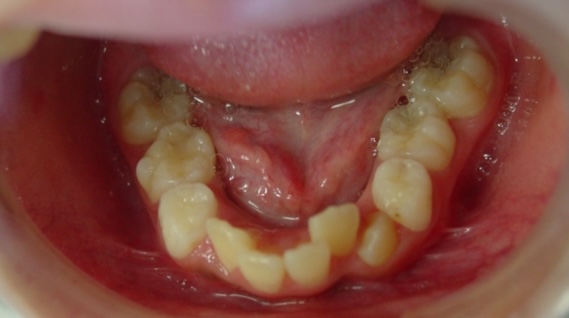

症例1-①

症例1-①の写真をご覧ください。著しく顎が小さく左の上下犬歯の萌出スペースがほとんどありません。ここで、歯ならびの相談に行くとおそらく将来、永久歯を抜くことになると言われることでしょう

口腔内を見ただけで、検査をすることなく、ショックな宣言を受けますが、そこには、医学的根拠による何の説明はありません。ここで、多くの場合、この二つのパターンのことを言われるでしょう。永久歯が生えそろってからきてください、またはとりあえず、顎を広げる治療してみましょう。